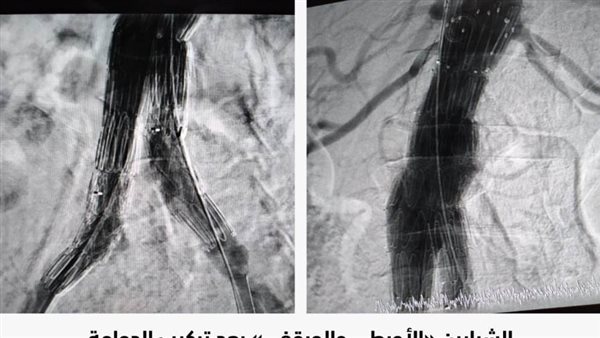

وأضافت الهيئة، أن الإجراء الأول تضمن التعامل مع انسداد الشرايين الطرفية بالطرفين السفليين للمريض من خلال عمل توسيع بالبالون، فيما شمل الإجراء الثاني فى نفس العملية التعامل مع مشاكل الشريان الحرقفي الأيمن والأيسر والأورطي للمريض عن طريق تركيب دعامات مغطاه ذات مقاومة عالية للانسداد باستخدام تقنية (CERAB)، مؤكدة استقرار الحالة الصحية للمريض وخروجه من المستشفى بحالة صحية جيدة.

جدير بالذكر، أن تقنية CERAB، Covered Endovascular Reconstruction of Aortic Bifurcation، تعني استخدام دعامات مغطاة BeGraft وتركيبها عن طريق القسطرة بديلًا عن التدخلات الجراحية لإعادة بناء وفتح قناة جديدة داخل الشريان الأورطي والشرايين الحرقفية لإعادة الدورة الدموية للطرفين السفليين، وتعد هذه التقنية أملًا جديدًا لعلاج مرضي ضيق وانسدادات الشريان الأورطي والشرايين الحرقفية بعيدًا عن الحل الجراحي المعروف، بما يُجنِّب المريض التعرض لمشاكل ومضاعفات التدخل الجراحي والذي يحتاج وقتًا طويلًا لإجرائه، كما أنه لا يصلح لكل الحالات المرضية.